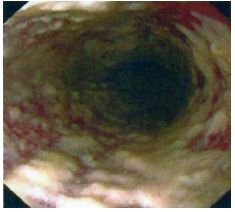

65. 28歲女性因8週的下腹絞痛合併腹瀉病史,接受進一步評估,她每天排便6至10次,其中有一至二次在半 夜,大便特徵為loose to watery with intermittent blood streaking。另外她有噁心及食慾變差現象,但無嘔 吐、發燒,也無服用藥物病史。身體檢查:體溫:37.8℃,血壓100/54 mmHg、脈搏96/min,腹部呈 現diffuse tenderness但無rigidity, guarding或rebound pain。大腸鏡檢查在升結腸、橫結腸及降結腸有如 附圖之發炎病灶,但是terminal ileum及rectum並無發炎現象,下列何者為最可能之診斷?

(A) Collagenous colitis (B) Crohn colitis (C) Ischemic colitis (D) Ulcerative colitis (E) Tuberculous colitis